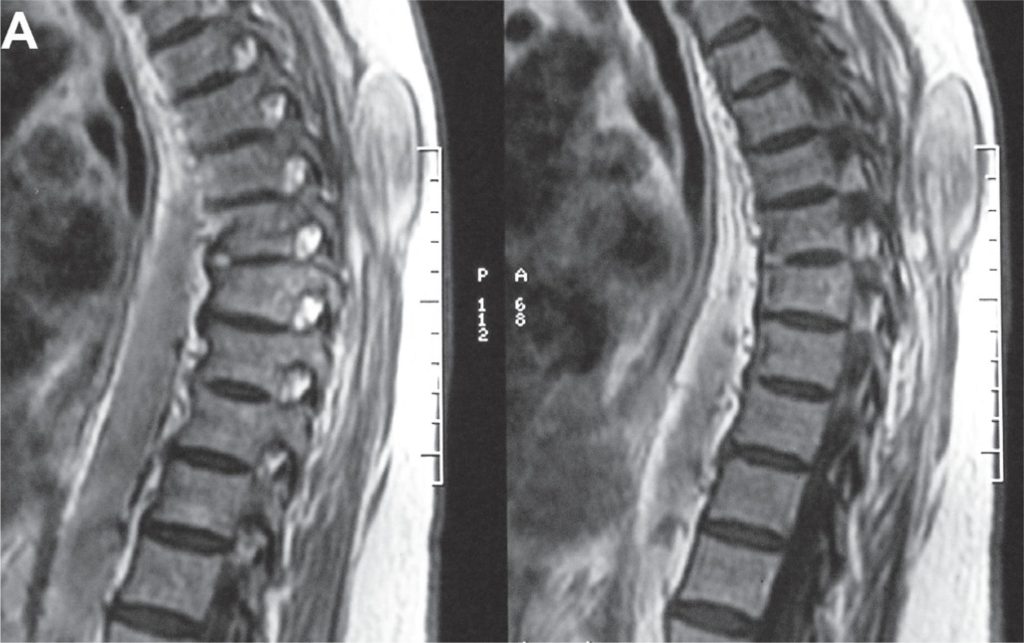

Uma senhora branca, de 84 anos, necessitou de tratamento neurocirúrgico devido a um neuroma na raiz direita de T12, após uma paraparesia progressiva. Contudo, 8 meses após a cirurgia, observou-se um edema paravertebral indolor e não pulsátil. Um exame de ressonância magnética revelou um grande tumor paravertebral hiperintenso à direita, em imagens ponderadas em T1 e T2. Uma massa paravertebral bem delimitada, não associada ao sistema nervoso central, foi identificada durante a cirurgia. Esse tumor foi removido completamente e definido como desmoide. Não havia história pessoal ou familiar de polipose. O quadro teve um bom desfecho e a paciente faleceu 3 anos depois, devido a outras complicações clínicas.